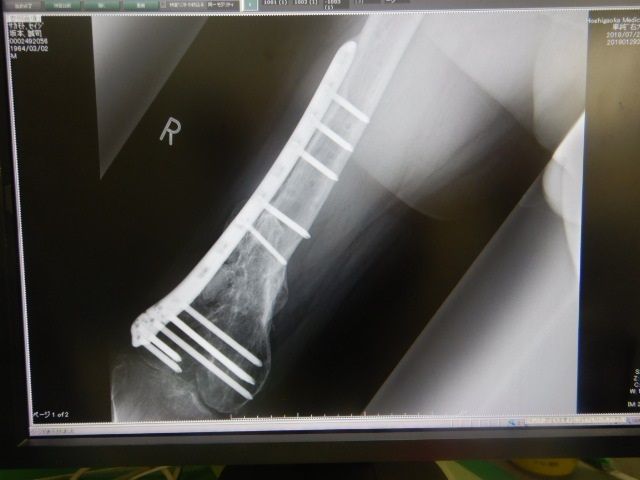

±¦ÂȾǯÄê´ü·ò¿Ç

Ⱦǯ¤Ë°ìÅ٤α¦ÂÄê´ü·ò¿Ç¤¬ºòÆü¤Î·îÍËÆü¤À¤Ã¤¿¤Î¤Ç

ÆóÏ¢µÙ¤Ë¤Ê¤ê¤Þ¤·¤¿¤¬

Î×»þµÙ¶È¤ò夤¤ÆÉ±¡¤Ø

¿Í¸ý¹ü¤â¤«¤Ê¤ê¤¯¤Ã¤Ä¤¤¤Æ¤¤Æ¤Þ¤¹¤¬

¥×¥ì¡¼¥È¤Î½üµî¤ÏºÆ¹üÀޤΥꥹ¥¯¤¬

¤¢¤ë»ö¤«¤é½üµî¤·¤Ê¤¤Êý¸þ¤Ç¤¹¡£

¤Ç¤âÅߤˤʤë¤È¥×¥ì¡¼¥È¤¬Î䤨¤Æ

Äˤ¤¤ó¤Ç¤¹¤è¤Í¤§¡Ä

¤Þ¤¡»ÅÊý¤¬¤¢¤ê¤Þ¤»¤ó¡£